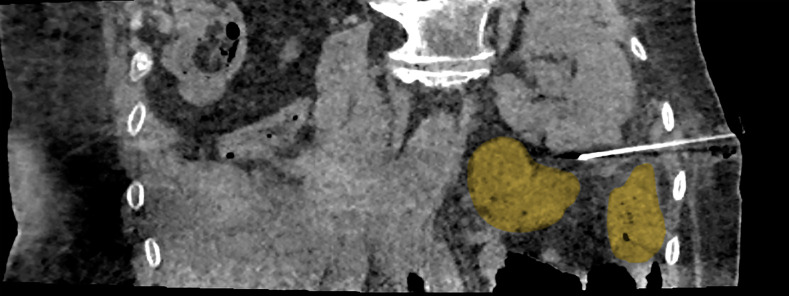

Aim: This study presents our experience with using percutaneous cryoablation (PCA) to manage recurrences and new masses in previously operated kidneys.

Materials and methods: We conducted a retrospective data analysis to evaluate patients treated with PCA for tumor recurrence or residual disease in the postresection bed, excluding those with de novo or recurrent tumors in the contralateral kidney.

Results: A total of 23 individuals met the inclusion criteria. Of those, 14 initially underwent laparoscopic PN, and 9 were treated with open surgery. The median interval from the initial surgery to recurrence‑targeted PCA was 23 months (range, 7-228). The mean (SD) RENAL score on admission was 7.5 (1.9), and the median (interquartile range) tumor volume was 3 (1.6-4.5) ml. The median length of hospital stay was 23 hours (range, 6-55). There was no significant change in estimated glomerular filtration rate following cryoablation. All the recorded complications, except one, were grade I and resolved with hydration or treatment with nonsteroidal anti‑inflammatory drugs. No patient required dialysis in the perioperative period.

Conclusions: Imaging‑guided PCA is a feasible and effective treatment option for patients with renal tumor recurrences after PN.